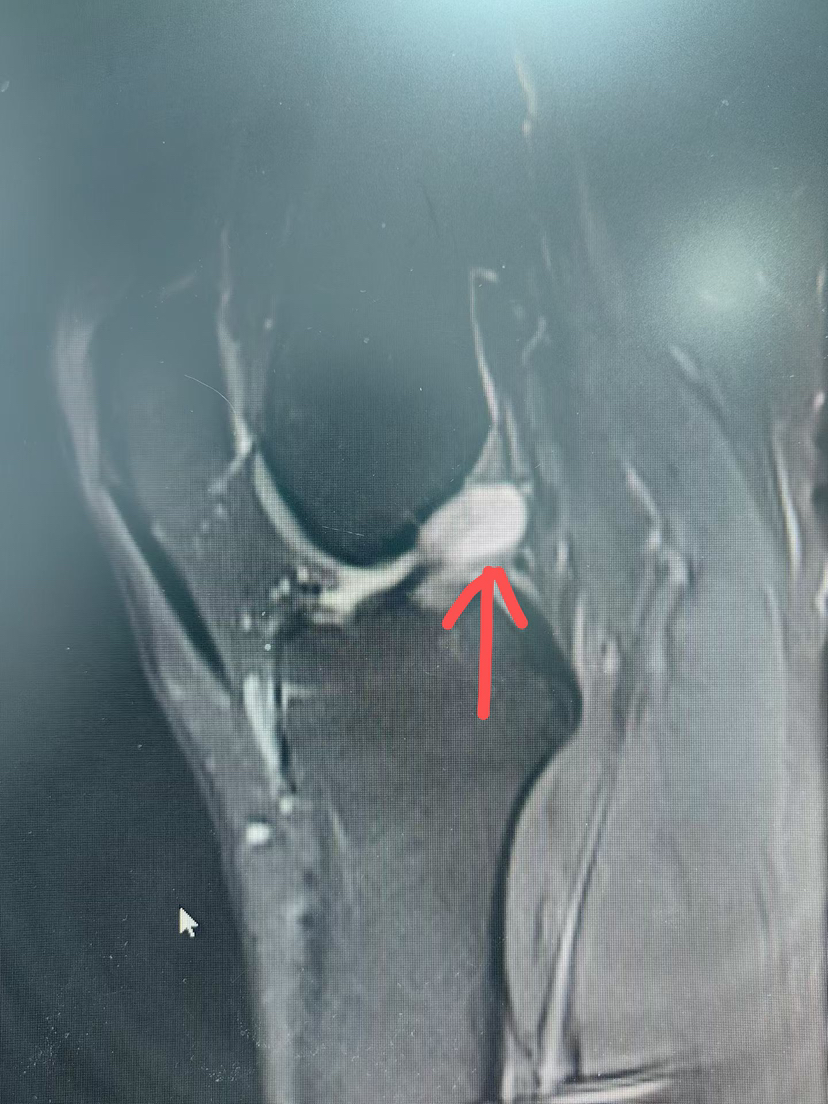

【 个别情况下韧带巨大囊肿完全或大部分侵蚀韧带,清理囊肿后,韧带纤维不多,不足以维持膝关节稳定,这种情况下需要进行韧带重建!

(囊肿巨大完全侵蚀韧带)